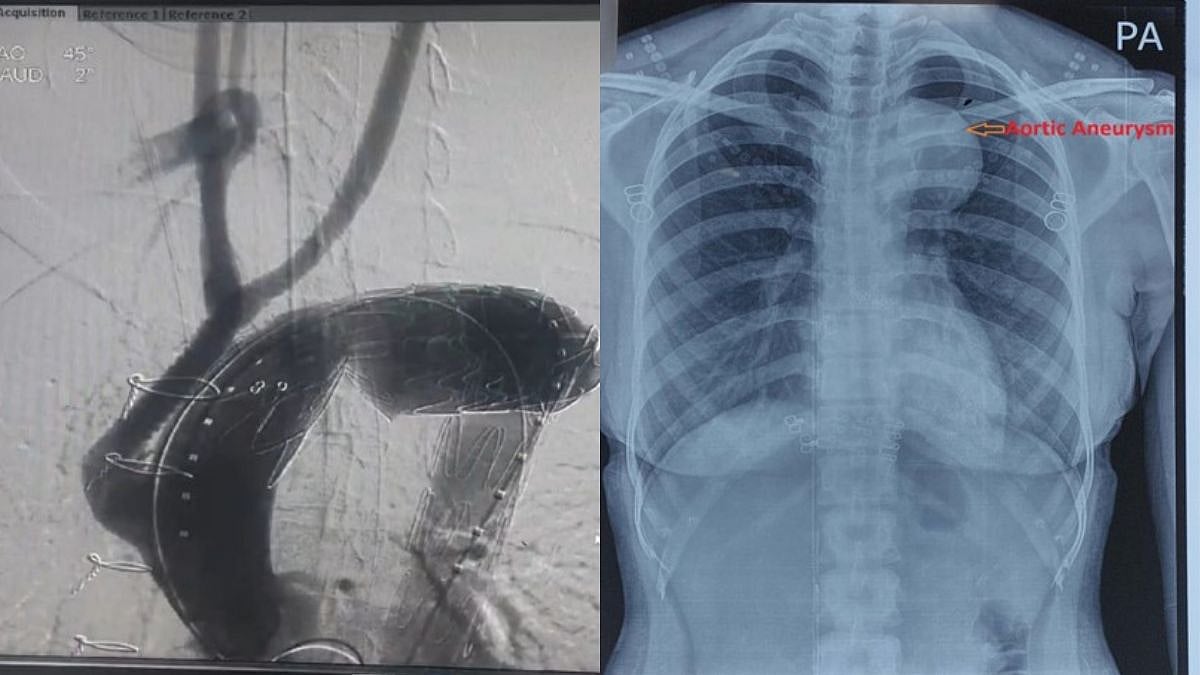

(Left) An X-ray of the aortic aneurysm of the patient; (right) the aortic aneurysm post Y-Graft and stenting procedures |

Western Railway’s Jagjivan Ram Hospital (JRH) at Mumbai Central adds another feather to its hat in the field of medical specialties. The Cardiovascular Department at JRH successfully conducted its first highly skillful complex cardiovascular interventional procedure which is also one of the rarest procedure to be performed worldwide and is also the first over Indian Railways. The procedure was performed on a 32-year old young mother.

According to Sumit Thakur, chief public relations Officer of Western Railway, the cardiovascular team of JRH recently conducted a highly skilled procedure. The 32-year old patient had a history of chest pain and features of heart failure, persisting for last 6 months. Upon thorough evaluation it was found that she was suffering from one of the rarest and life-threatening disease where her aorta was hugely dilated to a size of 61x 72 mm leading to ballooning of thoracic segment of aorta (thoracic aorta aneurysm) to a state of impending to rupture. All three great vessels of arch of aorta were involved indicating a state of near complete jeopardize of circulation to brain and both upper limbs. Looking at the critical and life-threatening clinical condition of patient, an emergency meeting among cardiologist, cardiac surgeon, interventional radiologist and cardiac anaesthesiologist was held and a risky, rare and complex hybrid (surgical and percutaneous) procedure was planned. The procedures were carried out successfully and the patient had an uneventful post-operative recovery and was discharged from the hospital.